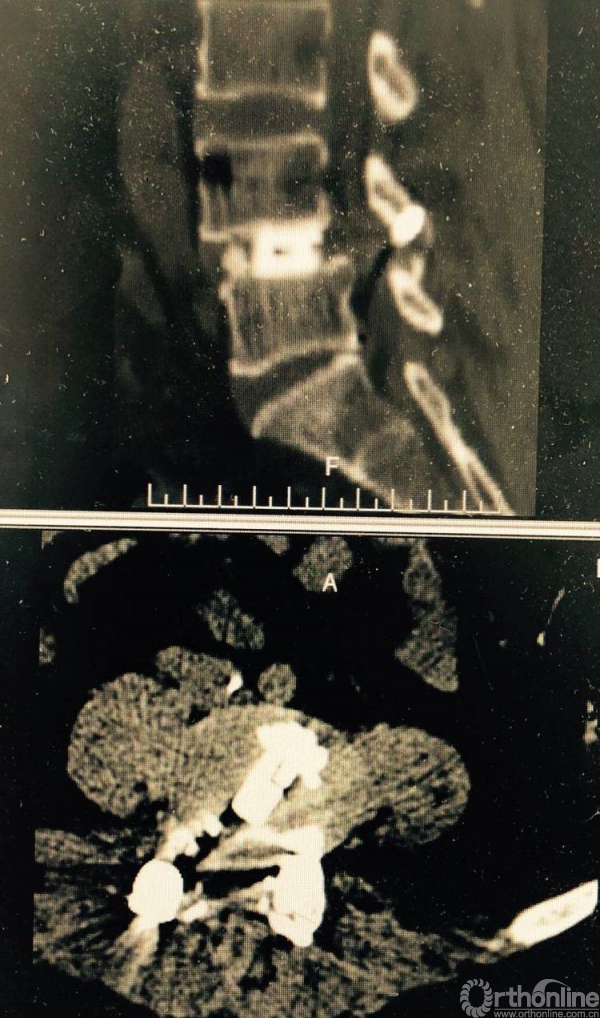

术前CT示L4/5重度椎管狭窄,腰椎滑脱合并硬膜囊受压。辅助检查如下:

术前CT

椎管狭窄减压较术前容积扩大

矢状位融合器、植骨位置及滑脱复位情况